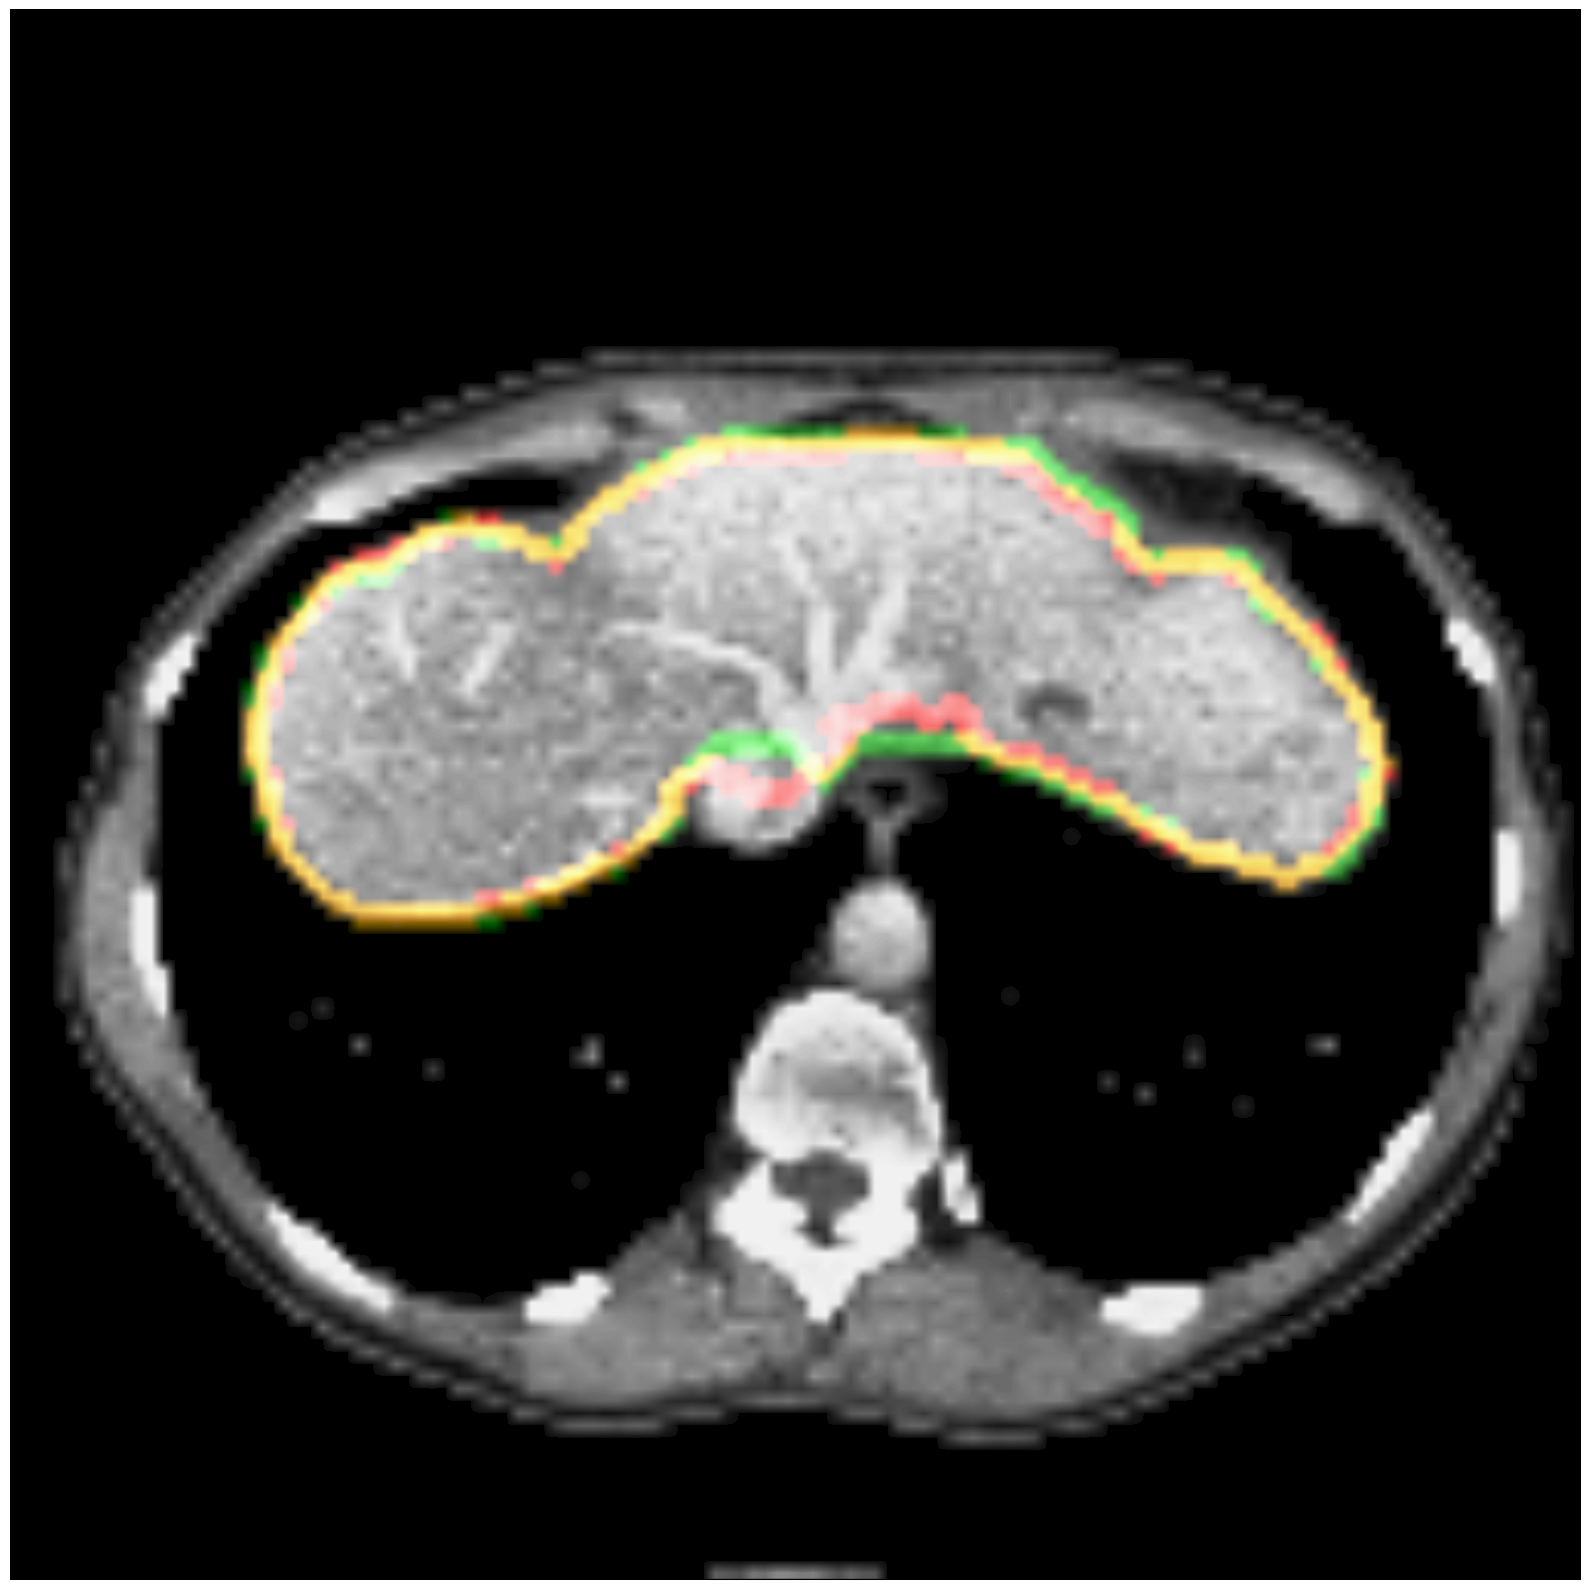

Some segmentation results at different vertebrae (top) and liver (bottom) areas are depicted in Fig. 2. The red contour corresponds to the outline of the prediction, green to the ground-truth and yellow to the overlap of the outlines.